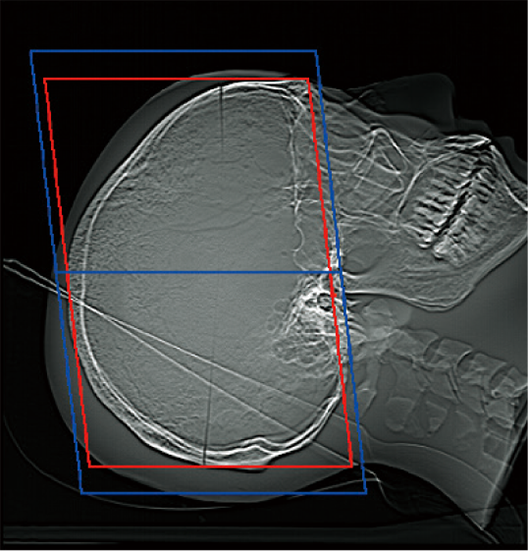

透過掃描定位圖影像,即可自動設定掃描範圍,有助於提升掃描位置的再現性與檢查效率,進而縮短整體檢查時間。

掃描範圍的邊界可依各醫療機構的作業習慣預先設定,實現符合需求的自訂化操作。操作者亦可隨時檢視與調整自動計算出的掃描範圍。*4

OM Line

SM Line

RB Line

Chest

紅色:自動設定位置

藍色:自動設定位置 + 設定邊界